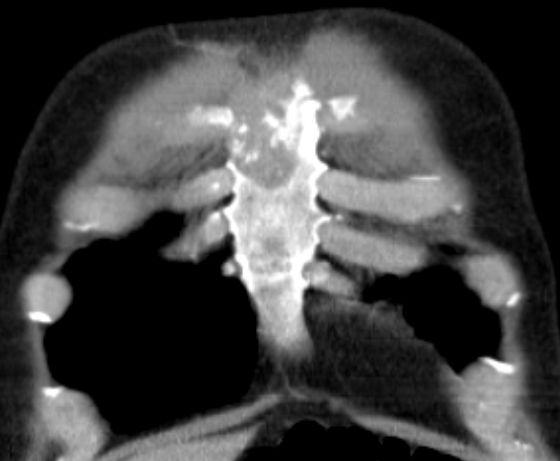

Schmerzhafte Sternummetastase.![]() |